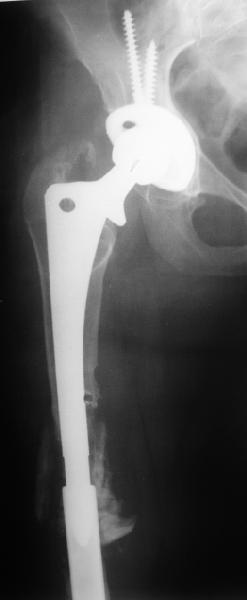

Female, rheumatoid, THA in 2003, car accident in 2006, failed plating. Nailing in Oct 2007. The nail is solid with hollow proximal part where the stem is docked. Last images are in 1 year after

nailing.